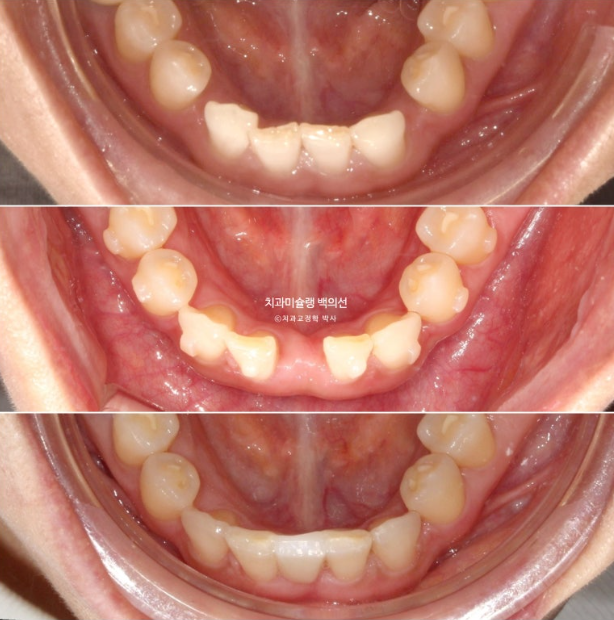

1년에 걸쳐 교정치료기간 동안 아래 앞니공간이 이동하는 모습은 이러합니다.

24.08~25.08

이제 아래 앞니 브릿지를 할 준비를 합니다.

아래 정가운데 앞니 이외에 다른공간은 모두 닫혔습니다.

25.08

뼈 상태를 고려하여 임플란트 보다는 브릿지가 낫다고 판단하여 브릿지로 앞니를 수복하기로 합니다.

좌우 인접치를 깎아서 한덩어리로 씌우는 방식의 브릿지 보다는 치아를 깎지 않고 뒤쪽에서 붙이는 형태의 메릴랜드 브릿지로 수복하기로 합니다.

메릴랜드 브릿지가 들어간 후 어태치먼트를 전부 제거하고 치료를 마무리 하였습니다.

선천적 결손으로 벌어져 있던 빈공간은 깔끔히 해결이 되었습니다.